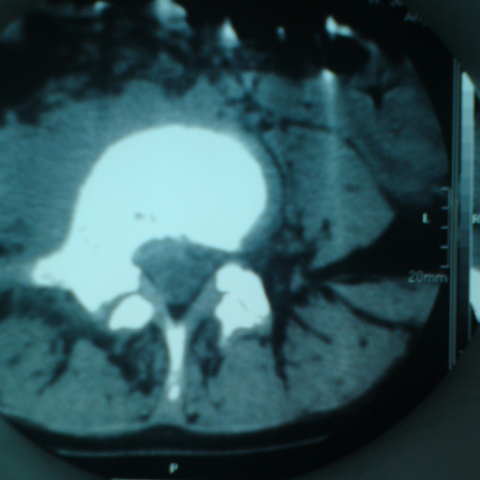

标题: CT27836:女 ,13岁,腰痛数月,加重一月,检查下腰部明显压 [打印本页]

标题: CT27836:女 ,13岁,腰痛数月,加重一月,检查下腰部明显压

考虑腰4椎体结核伴右侧椎旁及椎管右侧硬脊膜外脓肿形成。

考虑腰椎结核伴右侧椎旁及椎管右侧硬脊膜外寒性脓肿形成;建议必要时行mri检查。